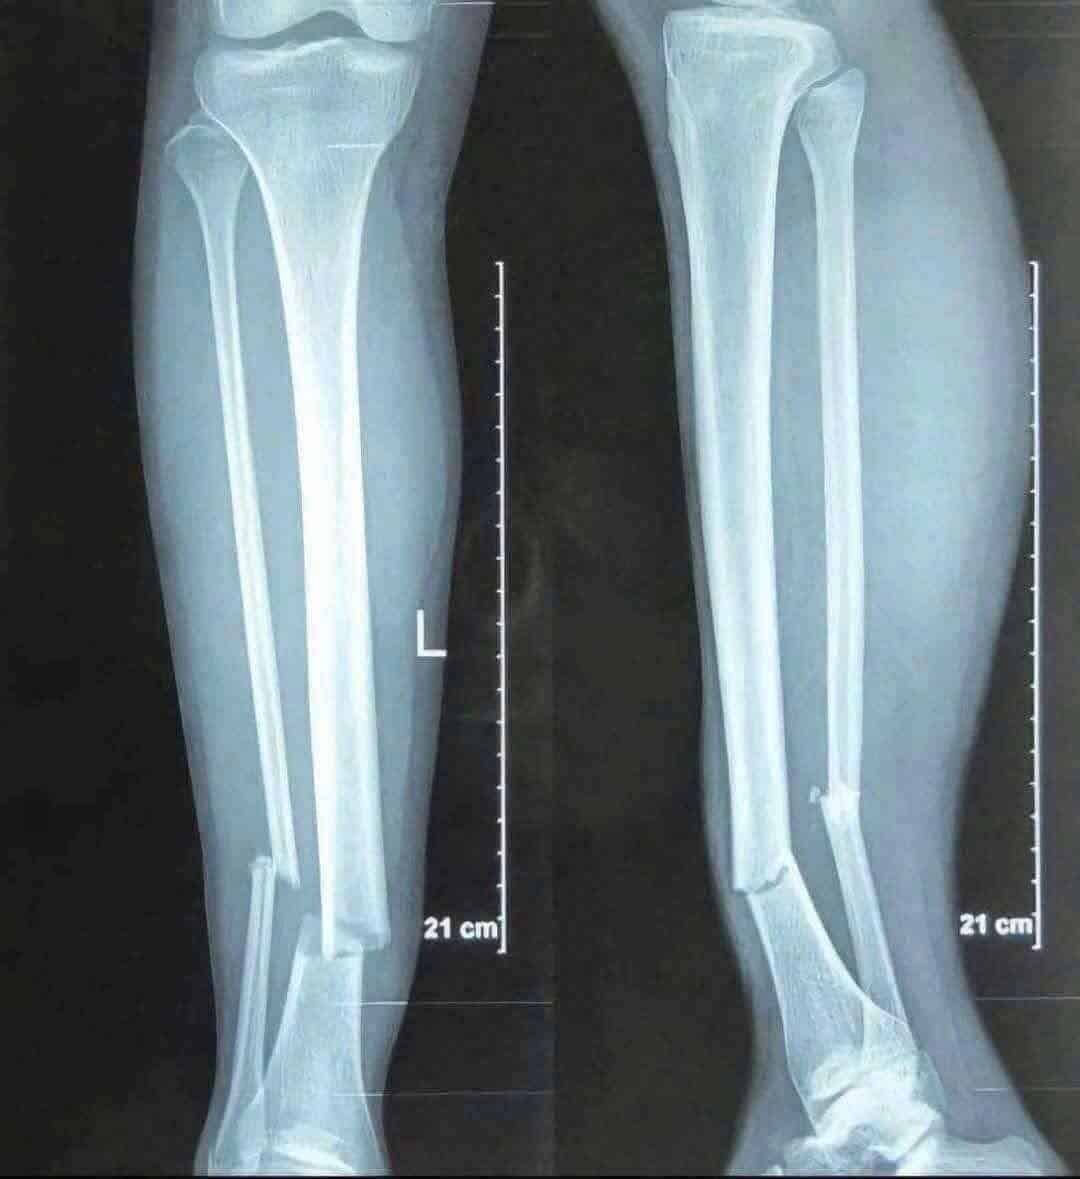

ล่าสุดมีการเปิดเผยออกมาว่า เหงียน ซวน ซอน ได้รับบาดเจ็บรุนแรงถึงขั้นขาหักสองท่อนทั้งสองข้าง โดยมีภาพเอกซเรย์ยืนยัน พร้อมทั้งมีรายงานว่าเจ้าตัวตัวต้องพักแข้งราว 5-8 เดือนด้วยกัน